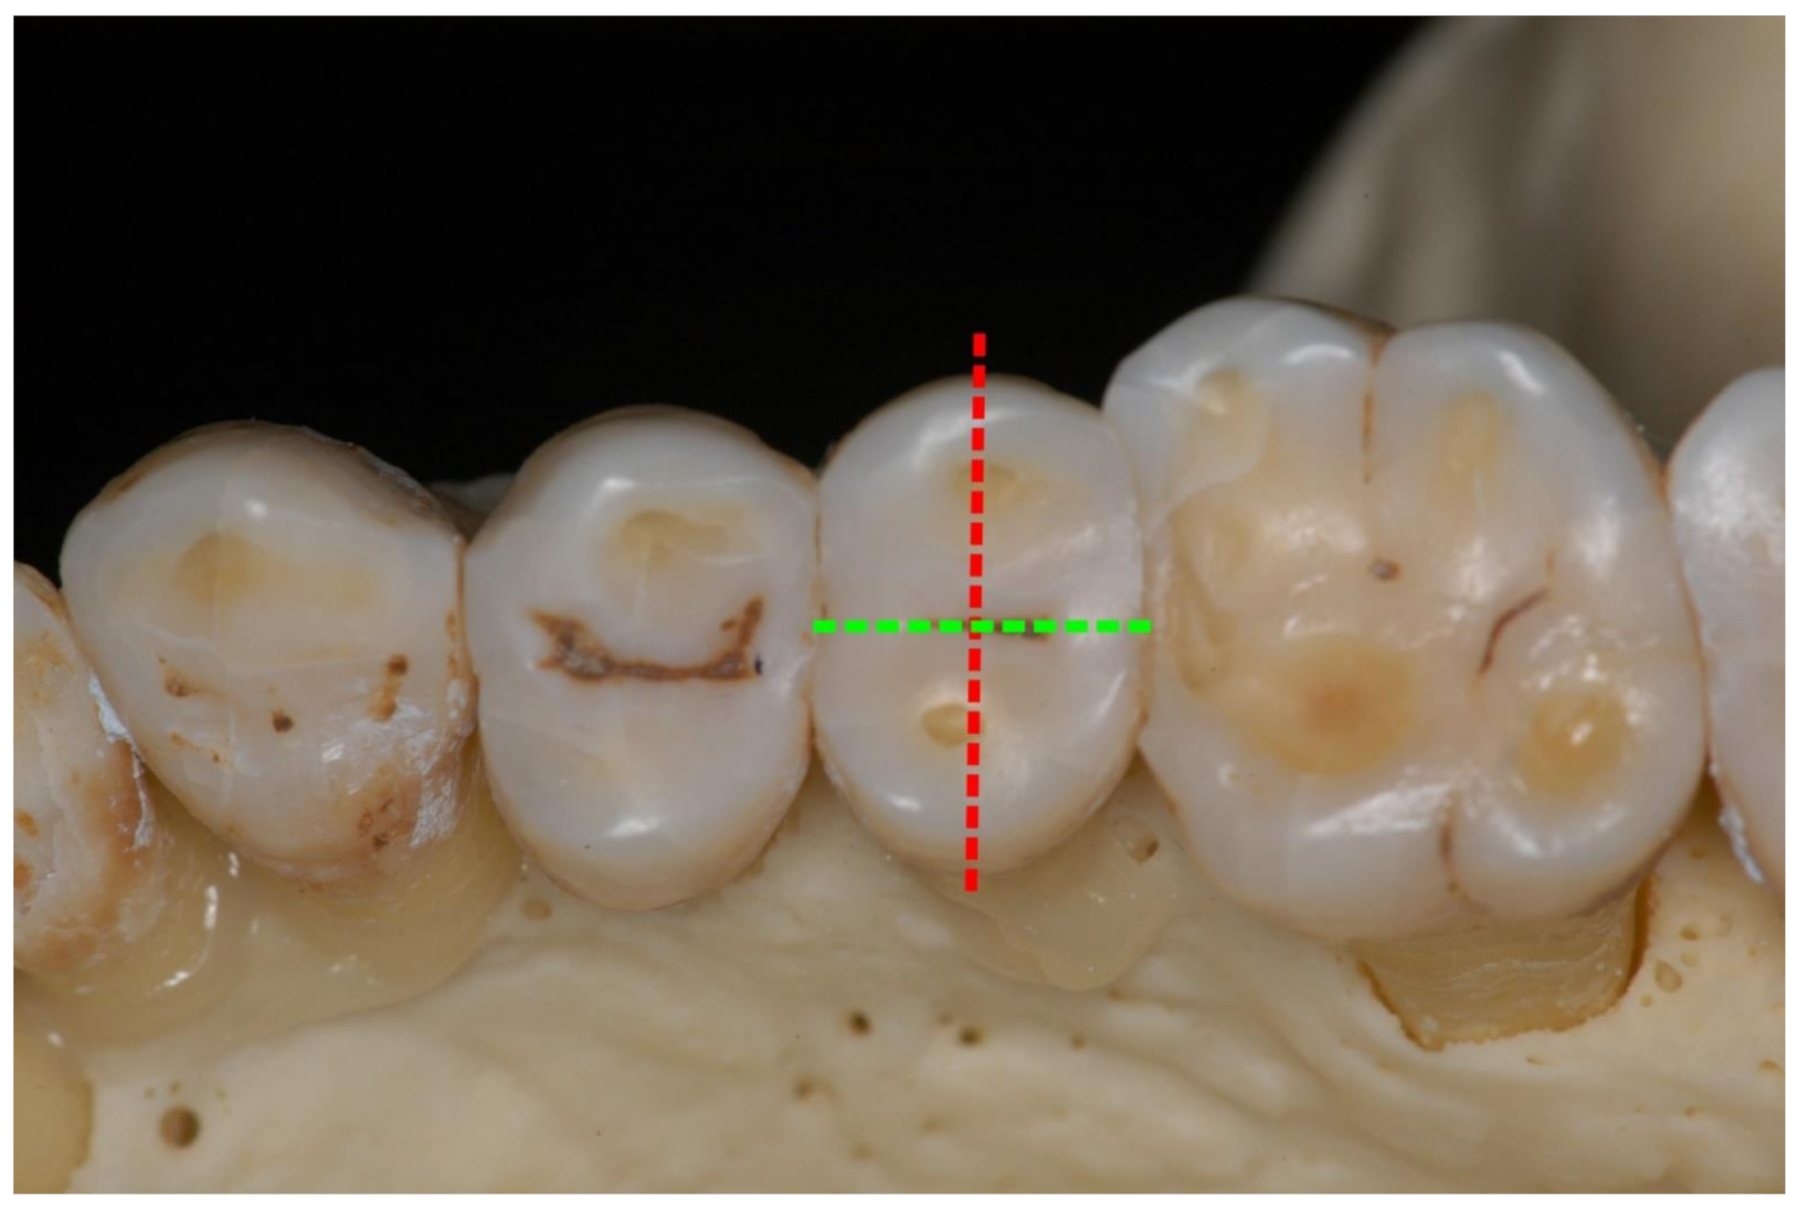

Unilateral mandibular condylar hyperplasia is a rare disease, where one condyle exhibits excessive growth [124,125,126]. A benign tumor of the long bones, osteochondroma, may also affect the mandibular condyle with similar consequences: Condylar growth leads to dislocation of the mandibular body in vertical and/or anterior direction. Asymmetry and occlusal imbalances are frequent consequences (Figure 10 and Figure 11). Treatment includes surgical remodeling or removal of the affected condyle and, if necessary, insertion of a neocondyle.

Figure 10.

Panoramic radiograph of a unilateral condylar hyperplasia on a 38-year-old female patient’s left side. Green dotted lines outline the condyles; arrows indicate non-occlusion in the left bicuspid and molar region. In this case, the panoramic radiograph gives an impression of asymmetry. However, CT and cone beam CT are superior in accuracy.

Figure 11.

Intraoral view of the same patient. Unilateral open bite on the left side and moderate mandibular midline shift are clearly visible. At present, occlusal stability is maintained by an intraoral splint until a definite correction with crowns and overlays in the left mandible will be performed.